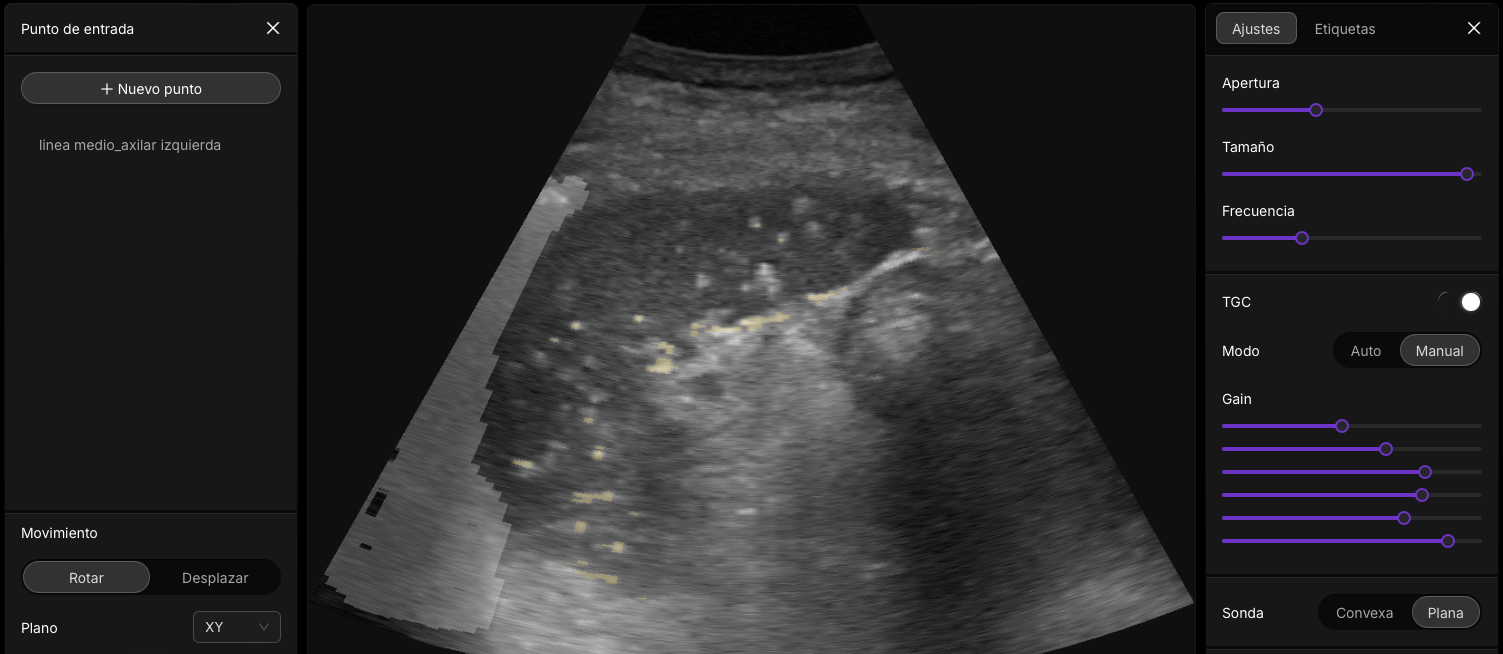

¡Importante! Al pulsar sobre la imagen accederás a un jugable docente.

Interacción Sonido con tejidos: Just do It!

Figura 5: Tipos comunes de transductores de ultrasonido ( si presionas en sobre la imagen podras ver una animacion gráfica de los diferntes tipos transductores )]

👉 Pulsa sobre la imagen para acceder.

Figura 6: Accede a Imagine Ultrasound Y Cambia de Sonda]